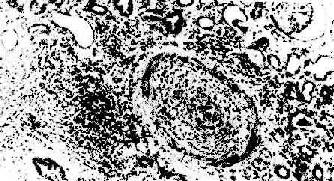

3.慢性排斥反应 慢性排斥是反复急性排斥的积累,其突出的病变是血管内膜纤维化,常累及小叶间弓形动脉。动脉内膜纤维化引起管腔严重狭窄(图4-7),导致肾缺血,表现为肾小球毛细管袢萎缩、纤维化、玻璃样变,肾小球萎缩,间质除纤维化外尚有中等量单核、淋巴细胞浸润。肉眼观,肾体积明显缩小,并有多少不等的瘢痕(“小瘢痕肾”)。包膜明显增厚并有粘连。患者肾功能呈进行性减退,其程度与间质纤维化和肾小球、肾小管萎缩的程度成正比。

肾移植慢性排斥反应

图4-7 肾移植慢性排斥反应

小叶间动脉管壁纤维化,管腔闭塞,内膜有中等量单核细胞浸润,管周组织内也有类似的细胞浸润